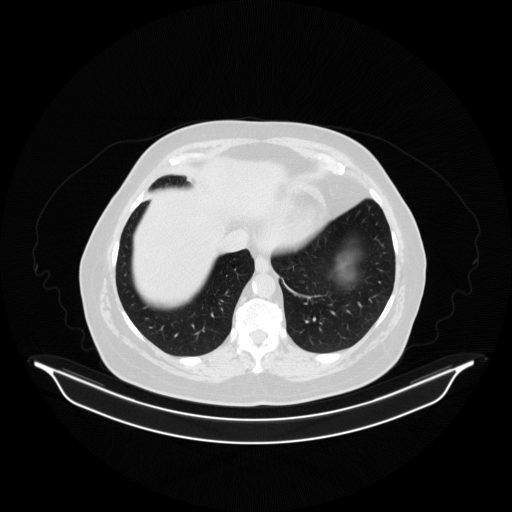

Image Grid

4Γ—3 grid: Rows show different image types (Original NATIVE, Reconstructed NATIVE, Original VENOUS, Generated VENOUS), Columns show windowing techniques (No Window, Lung Window, Mediastinum Window)

Original VENOUS CT scan

Lung window (WL -600, WW 1500 β†’ Low βˆ’1350, High +150)